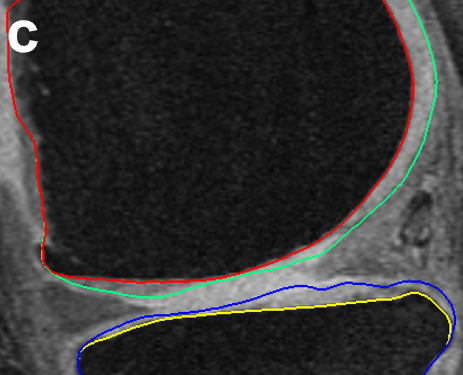

For analysis of the cartilage structures, accurate segmentation is a crucial first step. In clinical research there is a need for reproducible fully or highly automated segmentation as it offers consistent accuracy and speed over manual segmentation efforts. However, automated knee segmentation is challenging due to the thinning cartilage, appearance of osteophytes, bone marrow and cartilage lesions and surface fibrillation in MRI data. Several of these disease artifacts appear similar to the cartilage further increasing the segmentation complexity (Fig. 8a).

Fig. 7 qualitatively compares the segmentation accuracies between the gradient-based costs and the hierarchical classifier with respect to the independent standard. Both the femur and tibia are shown with their respective bone and cartilage segmentations showing good agreement between learning-based segmentation and the independent standard.